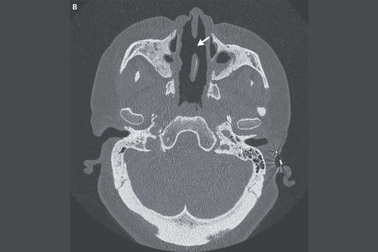

Người phụ nữ bị tiêu mất mũi do bệnh tự miễn hiếm gặpMột rối loạn tự miễn hiếm gặp đã phá hủy sụn và xương trong mũi của một phụ nữ, khiến mũi của bệnh nhân bị xẹp và lún xuống mặt.